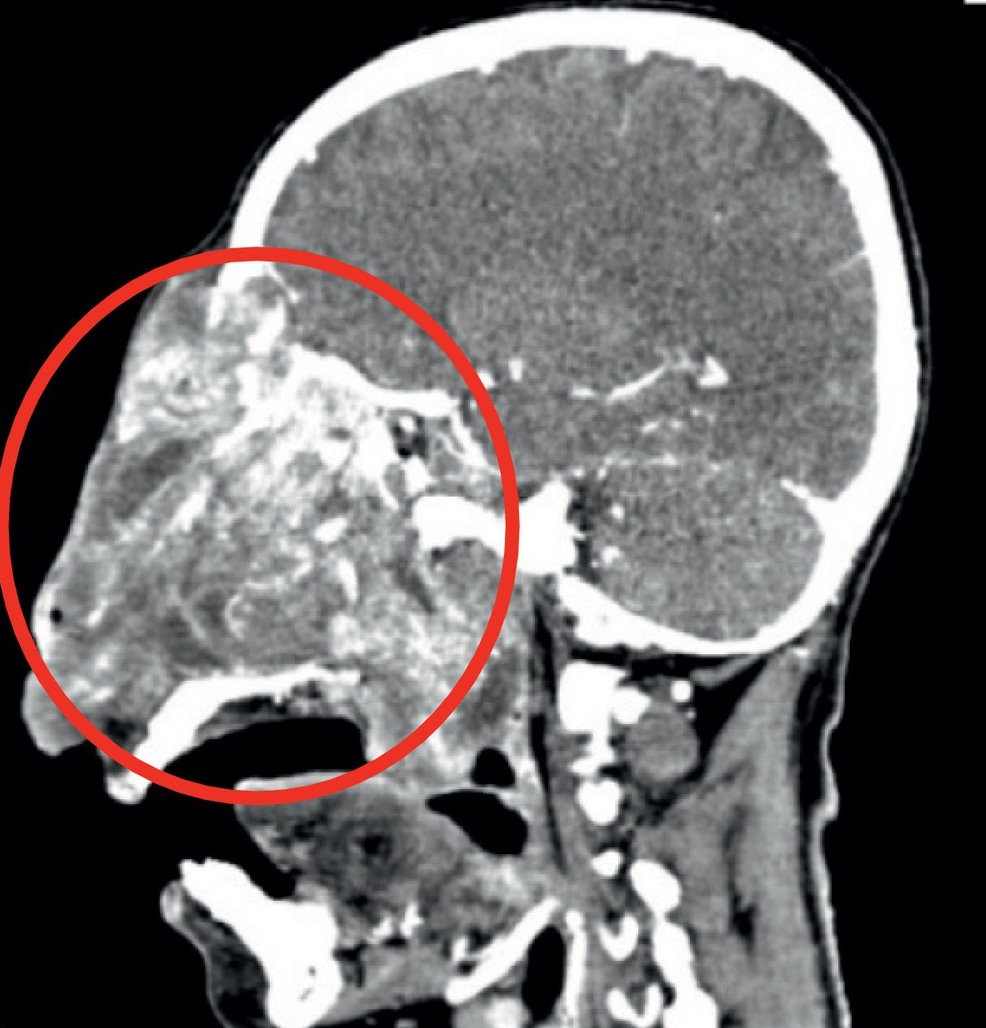

鼻咽腔内に生じる良性腫瘍「鼻咽腔血管線維腫」の男性の画像。

手術で切除。